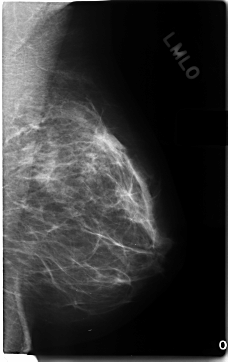

C_0197_1.LEFT_MLO

LEFT_MLO LINES 4696 PIXELS_PER_LINE 2952 BITS_PER_PIXEL 12 RESOLUTION 50 NON_OVERLAY